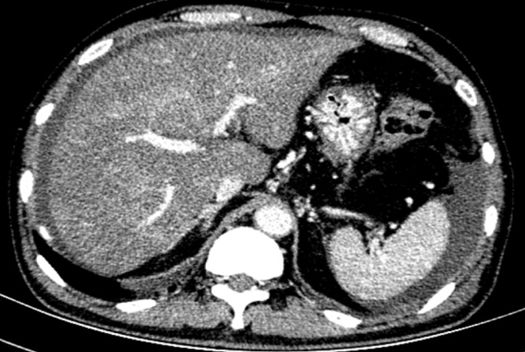

进一步检查及确诊:增强CT检查:下腔静脉肝段狭窄,内可见造影剂填充,肝脏异常强化(肝脏弥漫密度减低,门脉静脉期及平衡期显示肝脏不均匀强化,肝静脉周围呈片状明显强化,余肝实质呈轻度强化);腹部MRI:肝实质信号不均、肝静脉显示不清、腹水;肝脏病理活检:肝小叶结构未见异常,小叶中央为主的肝细胞片状退变坏死,灶性区域可见肝窦内淤血现象,形态提示缺血或淤血改变,致病因素包括药物/毒物、流出道梗阻(VOD、布加综合征)。免疫组化结果:CD34染色未见异常,CK7染色显示局部胆小管增生,局部肝细胞胆管化,HBsAg(-),特殊染色结果:Masson染色显示汇管区纤维组织增生,PAS、PAS+消化、铁、铜染色未见异常,网织纤维局部破坏。追问病史,患者起病前2月曾服用“三七粉”1月。最终诊断为吡咯生物碱相关性肝窦阻塞综合征。

CT: